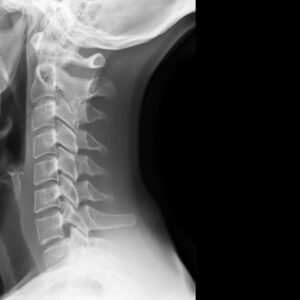

The human spine is a complex structure made up of vertebrae, intervertebral discs, ligaments, muscles, and nerves. Its role in supporting body weight, enabling mobility, and protecting the spinal cord makes it central to everyday function.

However, due to aging, injury, poor posture, and degenerative diseases, spinal conditions are among the most frequent musculoskeletal complaints. This article explores the most common spinal conditions and the treatment options available, ranging from conservative therapies to surgical interventions.

3. Spinal Stenosis

Spinal stenosis involves the narrowing of the spinal canal, which puts pressure on the spinal cord and nerves. It commonly occurs in the cervical and lumbar spine due to degenerative changes.

1. Degenerative Disc Disease (DDD)

Degenerative Disc Disease is not a disease per se but a term describing the natural wear and tear of intervertebral discs over time. Discs lose hydration and elasticity, reducing their ability to cushion the vertebrae. Watch Video

• Chronic, localized back pain (especially in the lumbar or cervical spine)